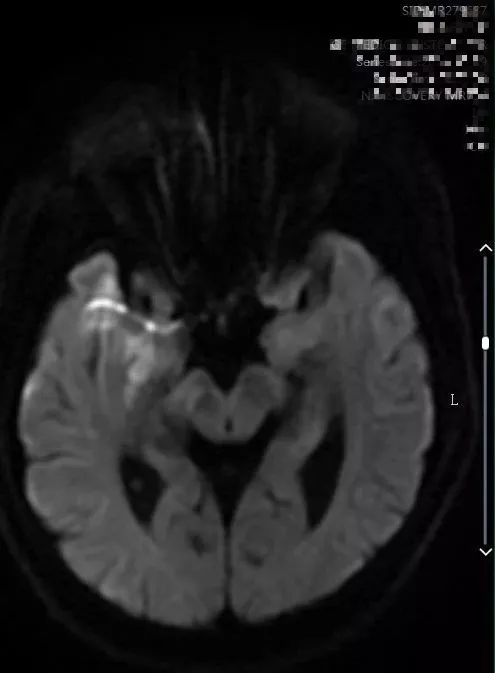

9:40分左右,患者逐渐开始出现烦躁、嗜睡,查体:言语不清,左侧肢体肌力0-1级,急查头颅MRI+MRA+颈部MRA阅片见,右侧基底节区急性脑梗死,右侧大脑中动脉闭塞。

头颅MRI+MRA(08-03日 11:50左右)

头颅MRI+MRA(2018-01-30日)